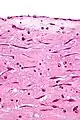

Micrograph of an atrial myxoma. H&E stain.

A myxoma is a rare benign tumor of the heart. Myxomata are the most common primary cardiac tumor in adults, and are most commonly found within the left atrium near the valve of the fossa ovalis. Myxomata may also develop in the other heart chambers.[1] The tumor is derived from multipotent mesenchymal cells.[1] Cardiac myxoma can affect adults between 30 and 60 years of age.[2]